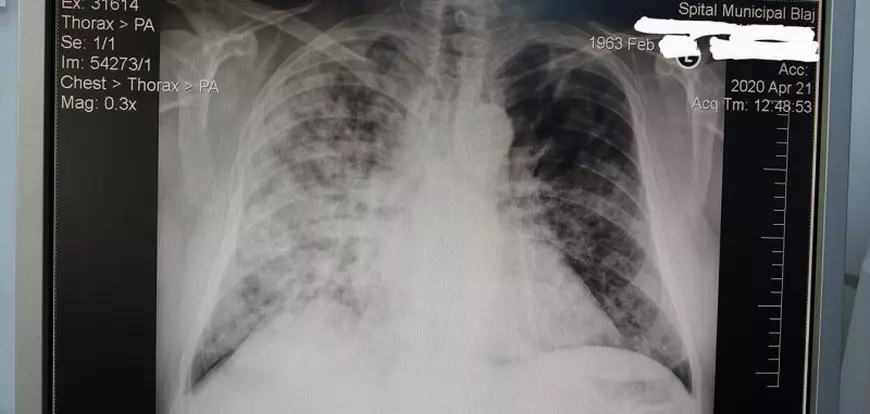

„Pentru cei care nu cred în existența virusului și în boala COVID și decesele provocate de COVID, fiindcă am văzut că există unii care au dubii în ultima perioadă, vă atașez poza rătăcită prin telefon la o radiografie a unui pacient de la spitalul din Blaj, de unde tocmai m-am întors. (…) Radiografii ca acestea am văzut foarte multe la spitalul din Blaj, cele mai multe dintre ele chiar mai urâte”, a spus Viore Mada, medic la Spitalul Judeţean de Urgenţă Alba.

Acesta a făcut publică o radiografie a unui pacient diagonosticat cu coronavirus, potrivit Alba24.

”Acesta a fost un caz ușor spre moderat și pacientul a scăpat cu bine, dar am avut și cazuri mult mai grave, de exemplu, soț și soție internați în același timp, soția a murit, din păcate, până la urmă pe secția de ATI”, a mai transmis medicul specialist Viorel Mada.

Doctorul a fost detașat pentru o perioadă de două săptămâni la Spitalul Municipal Blaj, unde sunt tratate cazurile medii şi grave de bolnavi infectaţi cu coronavirus în judeţul Alba.